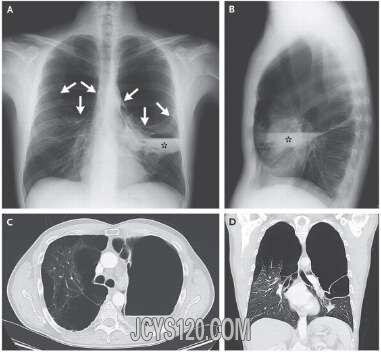

胸部X线检查表现为两肺尖及上叶的广泛性肺大疱(图A箭头处;图B),表明为消失肺综合征;左肺可见气-液平面(图A,B,C的星号处)。胸部CT证实以上结论(图C;图D)。

消失肺综合征,又称特发性肺大泡综合征,通常发病于较瘦的年轻男性吸烟者中。1987年提出的消失肺综合征影像学标准指出,该病表现为单/双肺上叶的巨大型肺大疱,占据胸腔的三分之一以上且压迫周围薄壁组织。肺泡中的气-液水平异常,提高了细菌重复感染的问题。